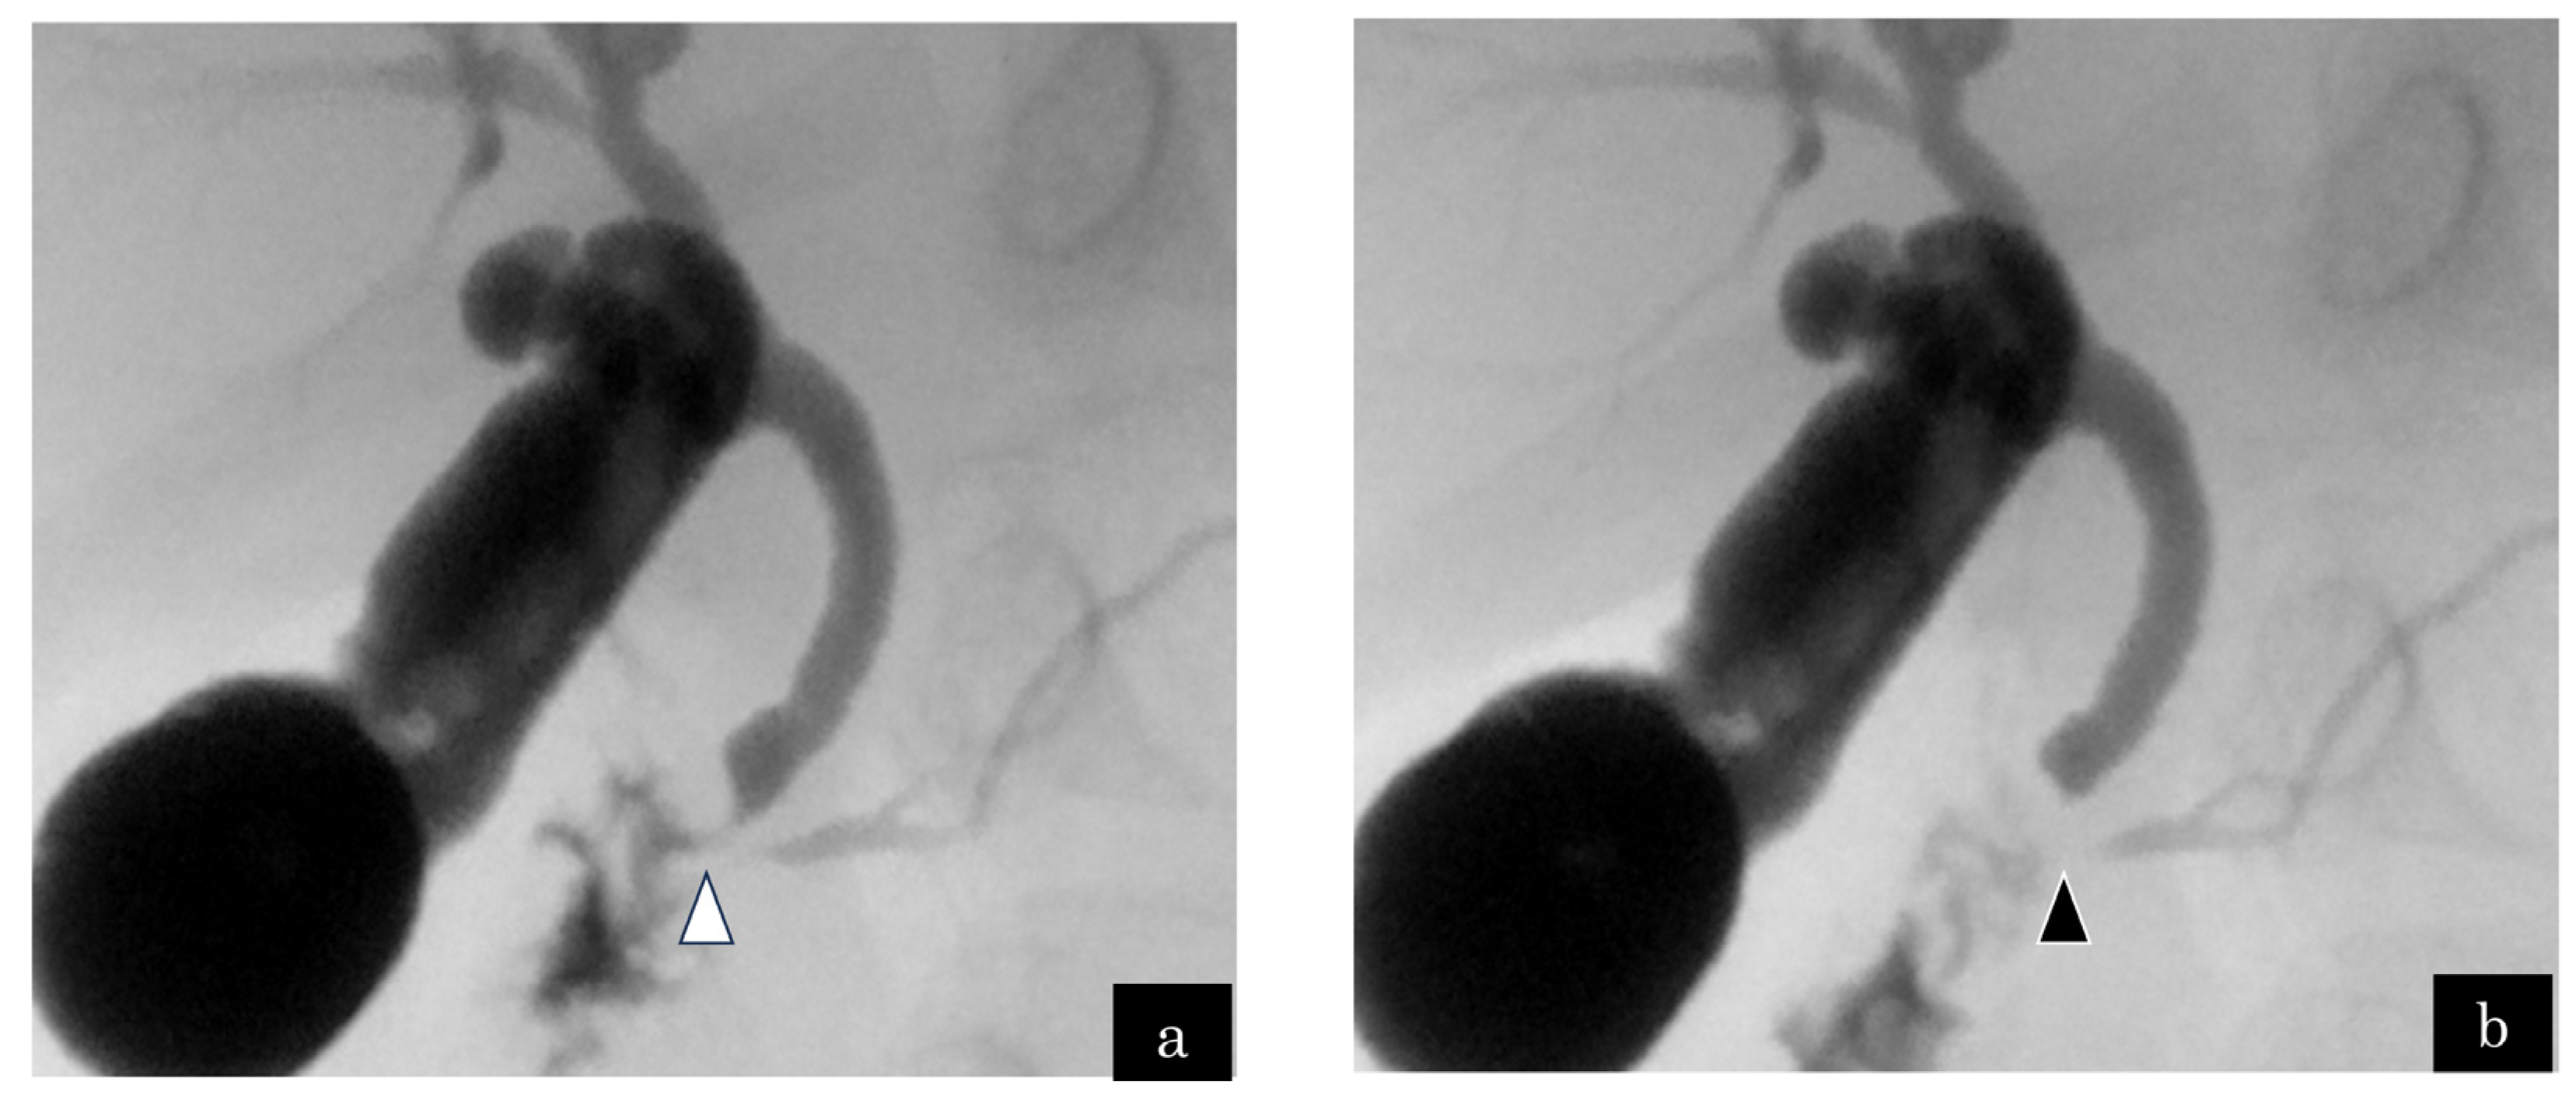

A 2-year-old boy presented with RAP. Genetic analysis indicated trisomy 13. MRCP demonstrated no abnormalities in the bile and pancreatic ducts, whereas ERCP exhibited a relatively long CC. Cholangiography revealed 3.5 and 6.3 mm lengths of the CC and SO segments, respectively. Communication between the bile and pancreatic ducts was interrupted during SO contraction (Figure 1a,b). Lipase was 768 IU/L in bile juice obtained via gallbladder intraoperatively. We considered PBR as a factor in the onset of RAP. The patient underwent bilio–jejunal anastomosis and was symptom-free postoperatively.

Figure 1.

Case 1: A 2-year-old boy who complained of recurrent acute pancreatitis. (a) The common channel (white arrowhead) was observed on endoscopic retrograde cholangiopancreatography via the main papilla. (b) The communication between the bile and pancreatic ducts was interrupted by the construction of the sphincter of Oddi (black arrowhead). The length of the common channel and sphincter of Oddi segment were 3.5 and 6.3 mm, respectively.

The length of CC increases with age, up to a maximum of 5 mm in children [5]. Generally, the length of the CC in pediatric PBMJ is considered to be >5–6 mm [5,24,41]. The pediatric ERCP studies of PBMJ [5,24,42] have revealed a long CC (>10 mm). Guelrud et al. [24] indicated the CC length of PBMJ to be between 16 and 33 mm (average: 22.8 ± 5.5 mm). We focused on the length of CC and SO segments. In general, a long CC is present in cases with PBMJ, and the pancreatic and bile ducts join at a site beyond the SO action. Matsumoto et al. [43] revealed that the length of the SO segment was 12.0 ± 1.1 mm (10–16 mm) and 10.0 ± 1.5 (8–16) mm in adult patients with PBMJ and the control group, respectively. Another study in children [24] revealed that the length of the SO segment was the same as that reported by Matsumoto et al. Therefore, no significant difference was observed in the length of the SO segment between normal cases and the PBMJ group. Hence, 6–7 mm CC would be subject to the action of SO. Kamisawa [6] and Horaguchi [7] reported a significant correlation between the length of CC and biliary amylase levels (p < 0.01). According to Horaguchi’s study [7], biliary amylase levels in cases with a CC length > 5 mm and > 6 mm were 12,333 ± 39,956 and 17,050 ± 447,031 IU/mL, respectively. This suggests that biliary amylase levels increase with the length of the CC. Since the length of SO segment does not change depending on the pathological condition, the length of the CC and PBR are considered to be related. The discussion of the association between the length of CCs and SO is advancing in adult cases and has not been much discussed in the pediatric field. A comparison of a report of PBMJ by Guelrud et al. [5] with our cases indicated that the CC length was 6–32 mm (average: 16.0 ± 5.6) vs. 3.5–5.5 mm (average: 4.6 ± 0.9) in children older than 1 year, demonstrating that the CC length was much shorter in our cases. Their CCs were slightly longer (0.3–1.1 mm: mean 0.6 mm) than the normal upper limit of CC in children in five cases (cases 1–5; Table 2). The CC was shorter than the SO segment in five cases in which the SO segment could be measured (Table 1). Furthermore, the communication between the bile and pancreatic ducts was interrupted during SO contraction under the fluoroscopy of cholangiography or ERCP. Therefore, PBR would occur due to the slightly long CC during childhood even if the SO was wrapped around the entire CC.